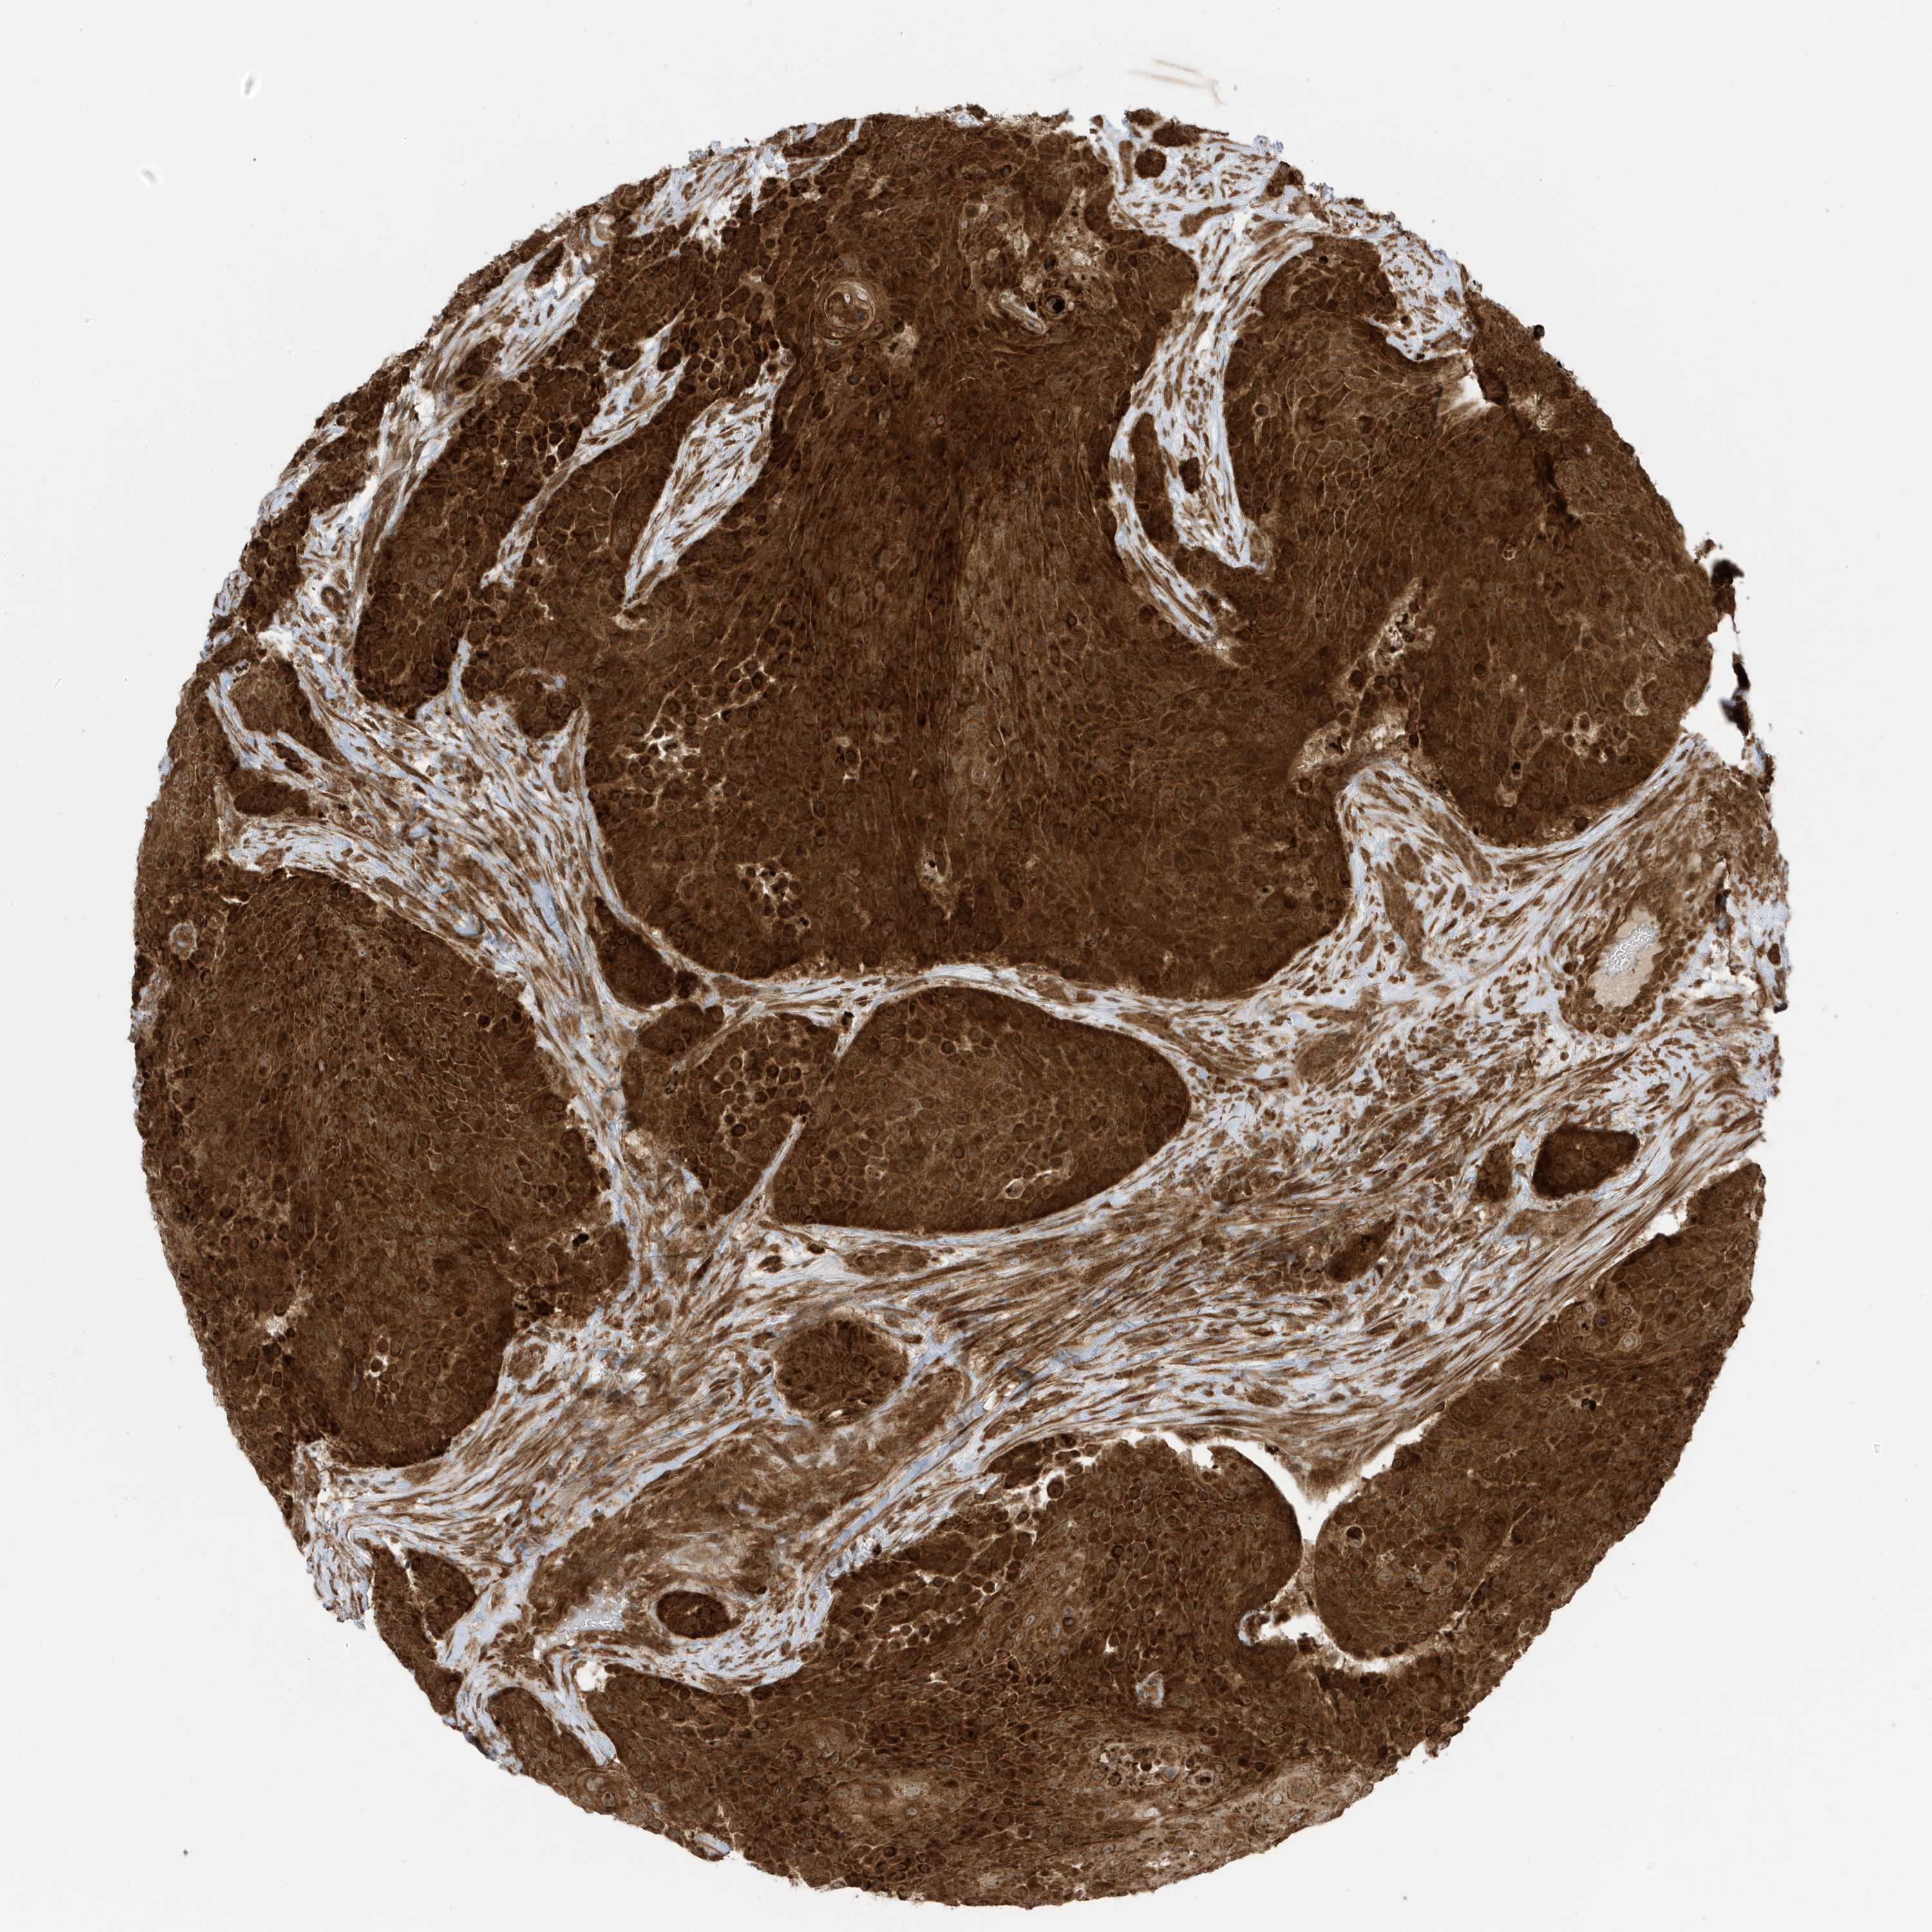

UROTHELIAL CANCER - Protein expressioni

A mouse-over function shows sample information and annotation data. Click on an image to view it in a full screen mode. Samples can be filtered based on level of antibody staining by selecting one or several of the following categories: high, medium, low and not detected. The assay and annotation is described here.

Antibody stainingi

Antibody staining in the annotated cell types in the current human tissue is reported as not detected, low, medium, or high, based on conventional immunohistochemistry profiling in selected tissues. This score is based on the combination of the staining intensity and fraction of stained cells.

Each image is clickable and will lead to virtual microscopy that enables deeper exploration of all samples and also displays staining intensity scores, fraction scores and subcellular localization as well as patient and tissue information for each sample.

Antibody HPA035399

Staining

High

Medium

Low

Not detected

Intensity

Strong

Moderate

Weak

Negative

Quantity

>75%

75%-25%

<25%

None

Location

Nuclear

Cytoplasmic/membranous

Cytoplasmic/membranous,nuclear

Urothelial carcinoma, Low grade

Urothelial carcinoma, High grade